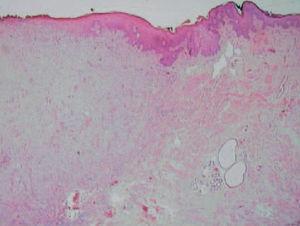

Histológicamente la tumoración estaba constituida por una proliferación fusocelular dispuesta en fascículos entrecruzados. Los núcleos de las células neoplásicas eran pleomórficos, alargados y de bordes romos, con marcada atipia y elevado índice mitótico (8 mitosis/10 campos de gran aumento). El tumor ulceraba extensamente la epidermis (fig. 1) y se extendía profundamente destruyendo la capa muscular lisa del escroto (figs. 2 y 3). El estudio inmunohistoquímico demostró una fuerte positividad para actina de músculo liso, desmina y vimentina, y negación para la proteína S-100, HMB-45 y citoqueratinas.

Fig. 1.—Tumor exofítico localizado en hemiescroto izquierdo.

Fig. 2.—Porción periférica del tumor en la que se aprecia cómo infiltra y destruye parcialmente la capa muscular del músculo dartos. (Hematoxilina-eosina, ×10.)